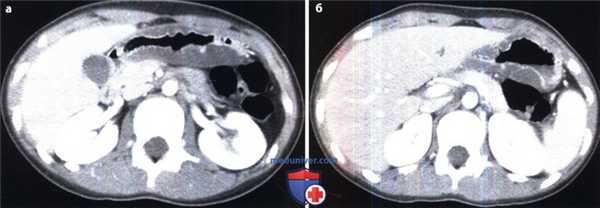

Гастрит, ассоциированный с Н. pylori: данные КТ.

(а, б) При КТ с контрастным усилением выявлено значительное утолщение стенки в области антрального отдела и тела желудка. Слизистая оболочка накапливает контраст в отличие от отечного подслизистого слоя, сигнал от которого приблизительно равен плотности воды.